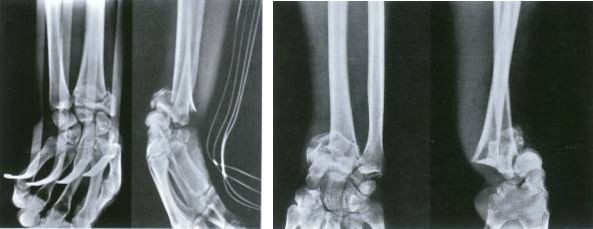

La fracture de la cheville est une fracture intra-articulaire.

Le but du traitement est de restaurer la structure anatomique normale des articulations.

Le moment de la chirurgie dépend de l'état des tissus mous.

Le moment idéal pour la chirurgie est avant l'apparition d'œdèmes et de cloques dans la zone de fracture.

C'est la pierre de marche pour que les gens se lèvent et marchent.La restauration de la structure anatomique normale du pied joue un rôle essentiel dans la position debout et la marche.

Comme pour les fractures de la cheville, le moment de la chirurgie dépend du degré et de l'état du gonflement des tissus mous.